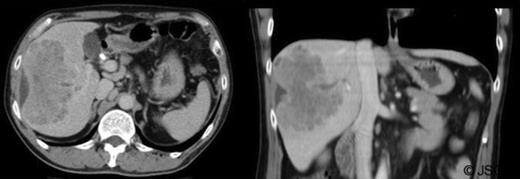

The mass had mild hyperintense signal on T2-weighted images and capsule retraction, suggesting a scirrhous lesion (figure 3); possibly cholangiocarcinoma.

T2 weighted abdominal MRI, coronal view displaying right lobe liver mass.